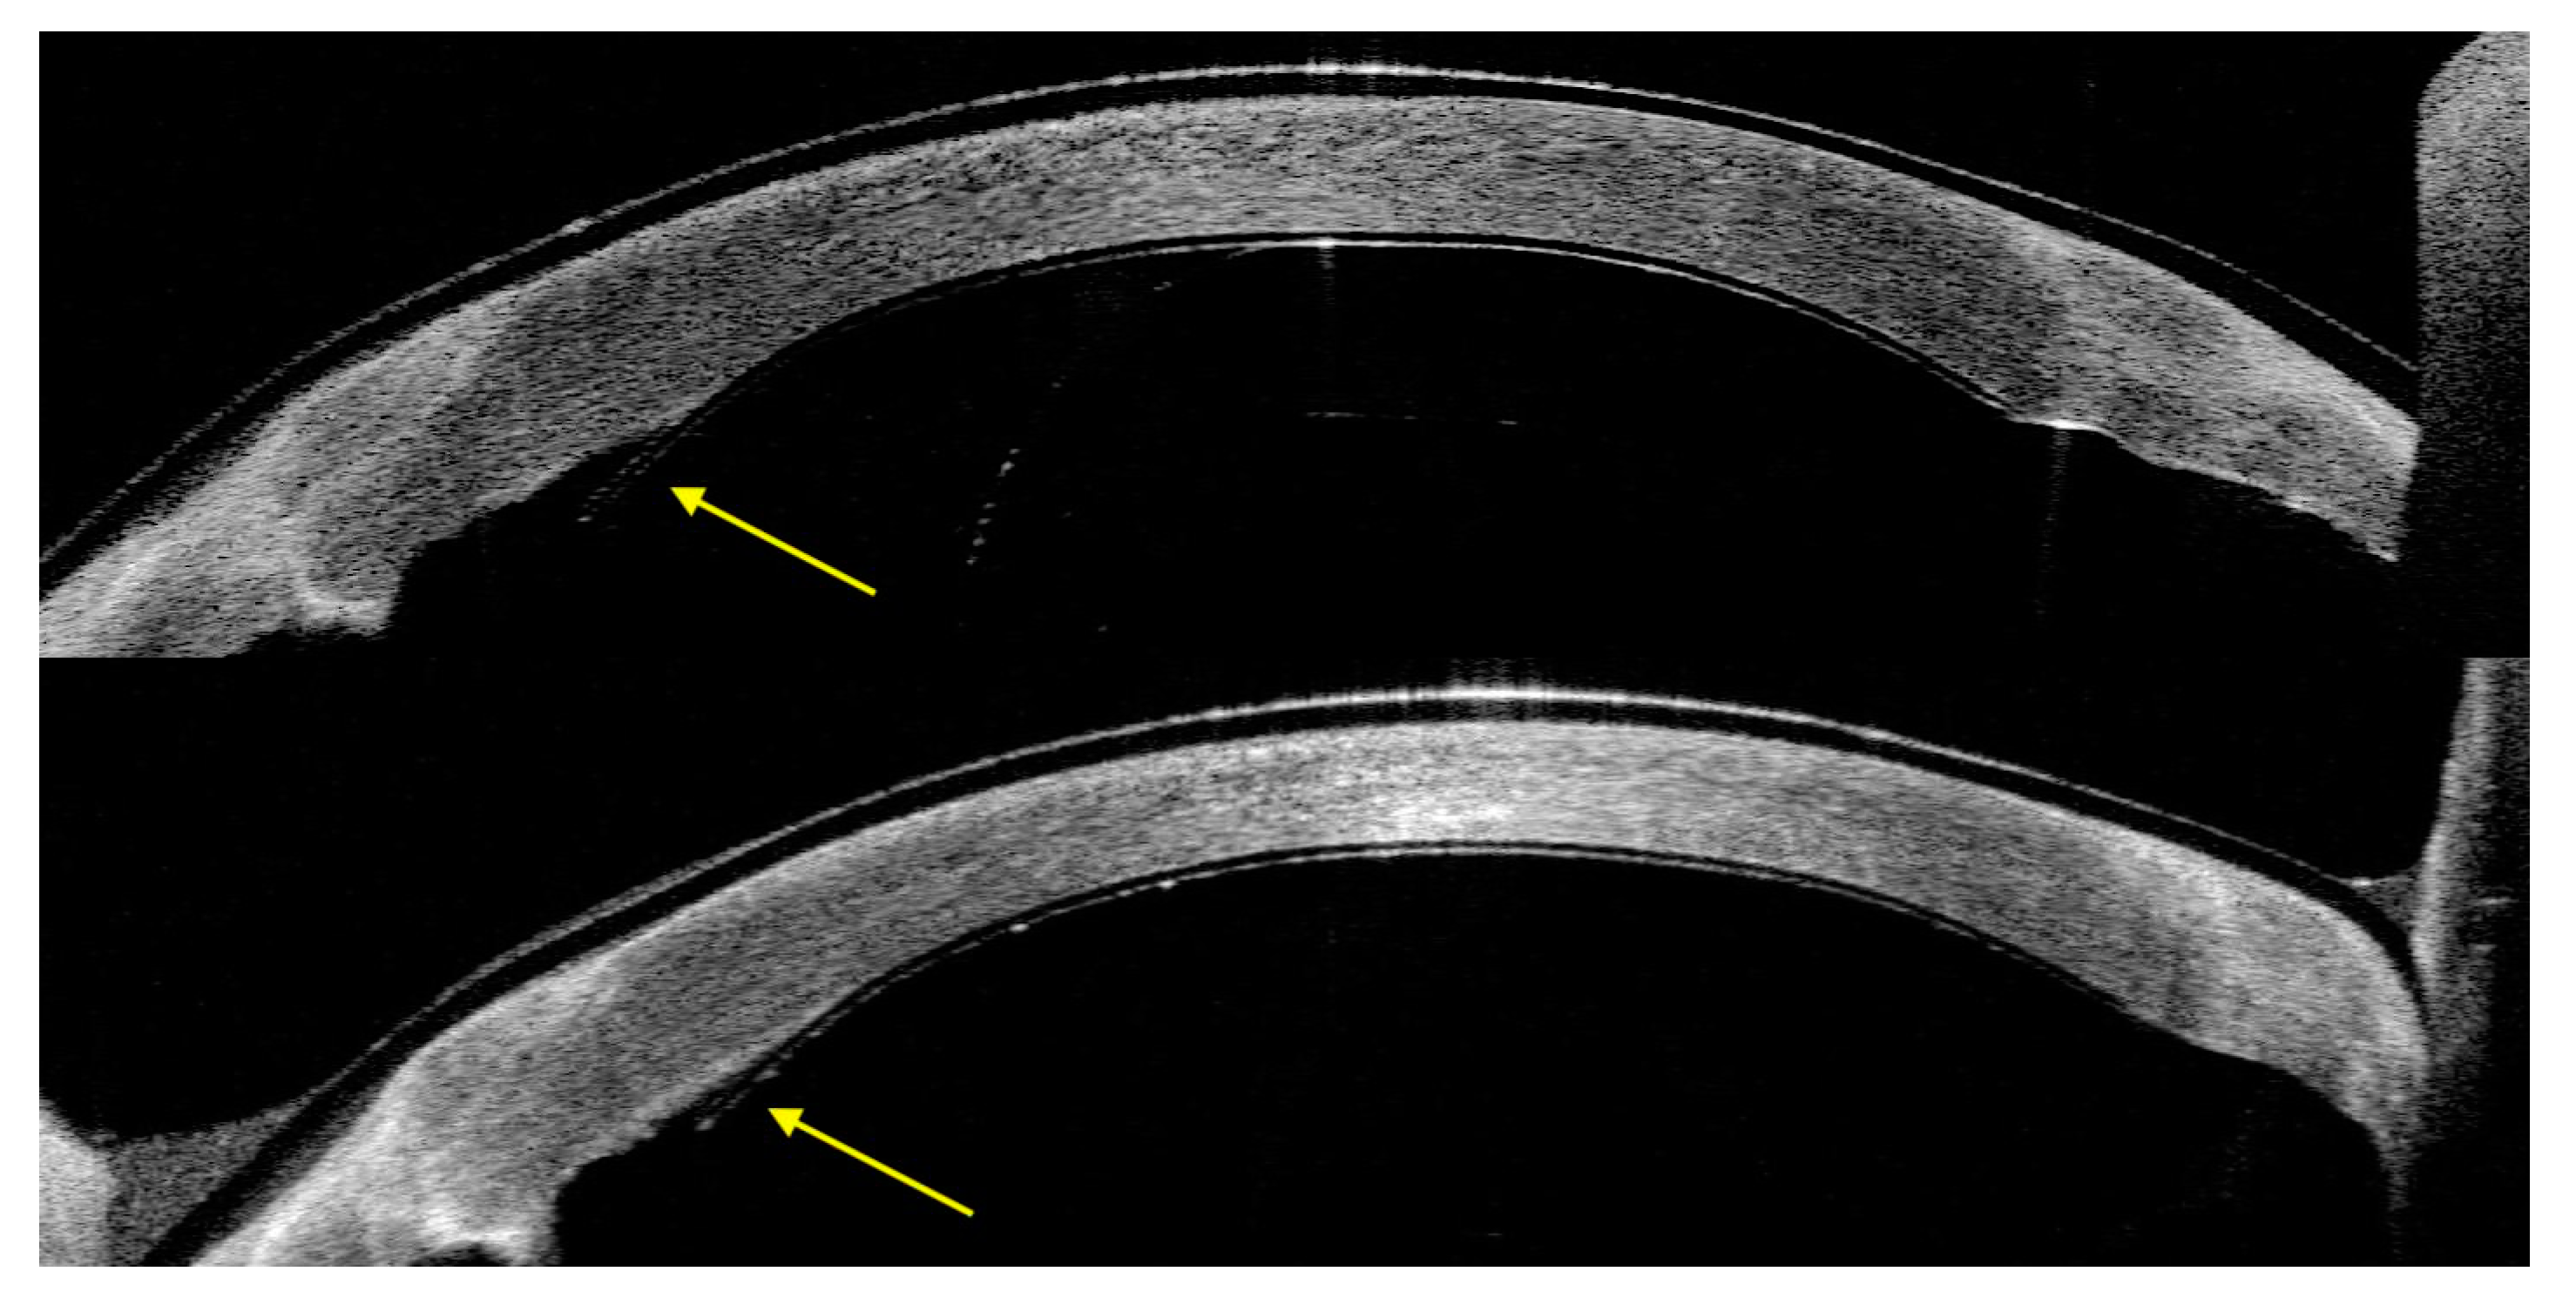

3.1. Case Series